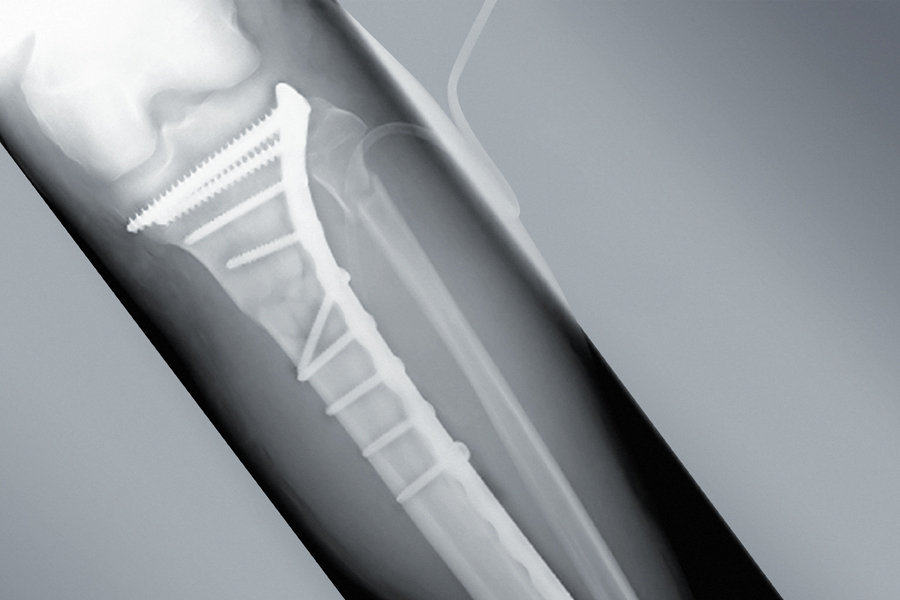

±ÙÀ§ °æ°ñ Àý°ñ¼úÀº ½½°üÀý¿¡¼ ÁßÁõÀÇ ÅðÇ༺ °üÀý¿°À» Ä¡·áÇϱâ À§ÇÑ ¼ö¼ú ¹æ¹ýÀÔ´Ï´Ù. ºñ±³Àû Àþ°í Ȱµ¿ÀûÀΠȯÀÚ°¡ ³»Ãø °üÀý¸é¿¡ ±¹ÇÑµÇ¾î ¼Õ»óÀÌ ÀÖ´Â °æ¿ì ±ÇÀåµÇ´Â ¼ö¼úÀ̸ç, ƯÈ÷ Àΰø°üÀýġȯ¼úÀÇ ½Ã±â¸¦ ´ÊÃß±â À§ÇÑ ¹æ¹ýÀ¸·Î ¼±ÅÃÇϰí Áٱ⼼Æ÷ À̽ļú°ú º´ÇàÇÏ¿© ½ÃÇàÇϱ⵵ ÇÕ´Ï´Ù.

±ÙÀ§°æ°ñÀý°ñ¼ú(HTO)ÀÇ

Àû¿ë´ë»ó

¹«¸ ³»Ãø °üÀý¸é¿¡ ¼Õ»óÀÌ ÀÖ´Â °æ¿ì

°üÀýÀÇ °¡µ¿¹üÀ§°¡ ÁÁÀº °æ¿ì

³»Ãø °üÀý¿°ÀÌ ÀÖ´Â °æ¿ì

ÁÖº¯ ÀδëµéÀÌ ¾ÈÁ¤ÀûÀÎ °æ¿ì

ºñ±³Àû Àþ°Å³ª Ȱµ¿¼ºÀÌ ³ôÀº ȯÀÚÀÇ °æ¿ì

¼ö¼ú ÈÄ ÁÖÀÇ»çÇ×

ȸº¹±îÁö ÃÖ¼Ò 3°³¿ùÀÇ ½Ã°£ÀÌ ÇÊ¿äÇϸç 2°³¿ù°ºÎÅÍ´Â ÀÏ»ó»ýȰÀÌ °¡´ÉÇϰí ÀçȰ¿îµ¿À» º´ÇàÇÕ´Ï´Ù. (ȸº¹±â°£ µ¿¾È¿¡´Â ¸ñ¹ßÀ̳ª º¸Çà±â »ç¿ë)

¼ö¼ú ÈÄ 6°³¿ù µÚºÎÅÍ Á¤»óÀûÀÎ ¿îµ¿À̳ª ÀÏ»ó»ýȰÀÌ °¡´ÉÇÕ´Ï´Ù.

ȯÀÚÀÇ »óÅÂ¿Í ¼ö¼úÀÇ ³»¿ë¿¡ µû¶ó ȸº¹¿¡ Á¶±Ý¾¿ Â÷À̰¡ ÀÖÀ» ¼ö ÀÖÀ¸¸ç »ÀÀÇ À¯ÇÕ Á¤µµ¿¡ µû¶ó ÇØ´ç ½ÃÁ¡À» °áÁ¤ÇÕ´Ï´Ù.